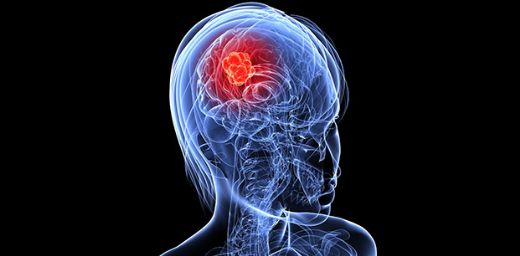

Beyine metastaz yaptığında şiddetli baş ağrıları ve hafıza karışıklıkları yaşanmasının nedeni, beyindeki artmış basıncın ve beyin dokusuna olan hasarın bu tür belirtilere yol açmasıdır. Beyin dokusu hassas olduğu için, metastazlar burada ciddi belirtiler yaratabilir. Bu nedenle, bu tür belirtiler görüldüğünde hemen bir doktora başvurmak önemlidir.